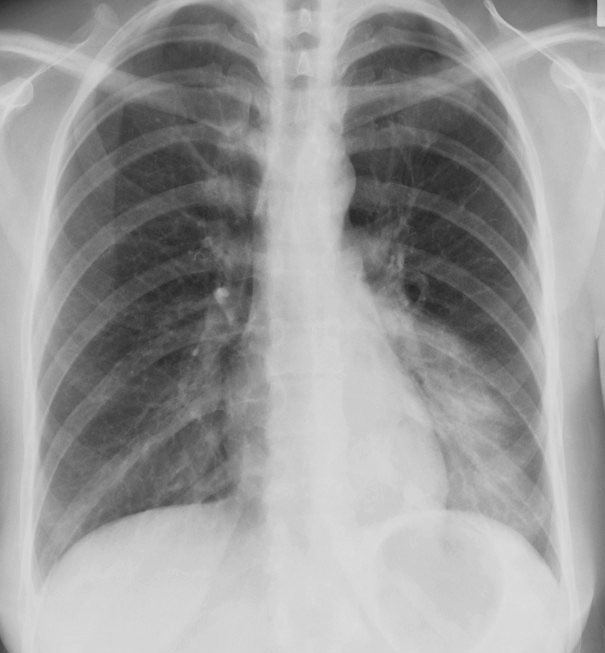

Gallery Pneumonia Case 10 LLL pneum PA

Case 10 LLL pneum PA